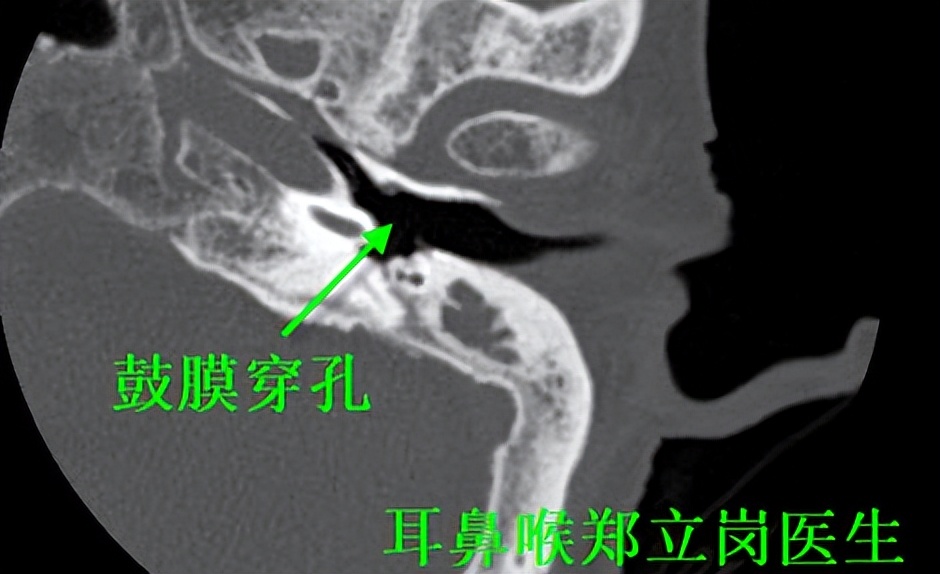

最近就有一位77岁的老人家,来到佛山复星禅诚医院找到耳鼻喉郑立岗医生,要求郑医生能为她解决多年的中耳炎。检查后发现老人家的左侧鼓膜大穿孔,做微创手术是没有任何问题的。就为她安排了手术,麻醉师插管全麻后就开始了手术,在耳内镜下不用做任何的体表切口,直接翻起外耳道鼓膜皮瓣,翻起皮瓣后可以看到鼓室中有少量的肉芽组织,予以清理,听骨链是完整的。取合适大小的耳屏软骨修剪后修补鼓膜,鼓膜修补好后检查了两遍确认没问题后就结束了手术。整个的手术用时约40分钟,非常的顺利。术后查房患者无明显的不适,无手术相关的并发症。